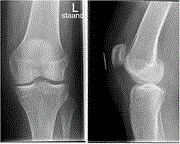

An avulsion fracture of the anterior cruciate ligament attachment to the lateral femoral condyle in an elderly patient: a rare finding

Brandsma A S E Annemarie and others

Journal of Surgical Case Reports, Volume 2020, Issue 4, April 2020, rjaa054, https://doi.org/10.1093/jscr/rjaa054